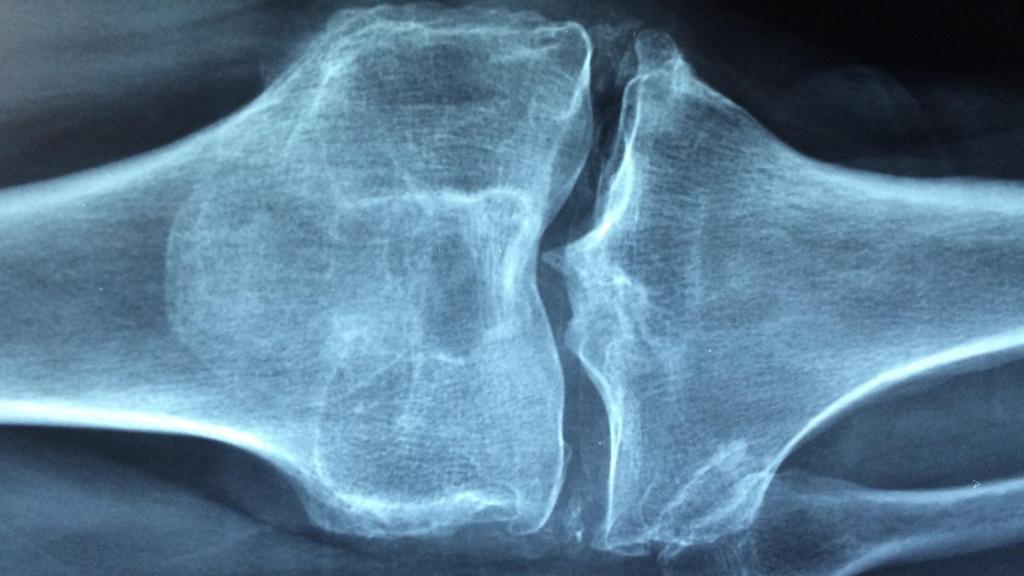

Osteoporosis.

Osteoporosis. Dr. Manuel González Reyes Pixabay.

Vivir con el temor a fracturarse una vértebra, un brazo o la cadera resulta fastidioso. Es lo que les pasa a quienes padecen osteoporosis, que literalmente significa “hueso poroso”. La enfermedad se caracteriza por la reducción de la masa ósea, y afecta al 30 % de las mujeres mayores de 50 años y al 8 % de los hombres.